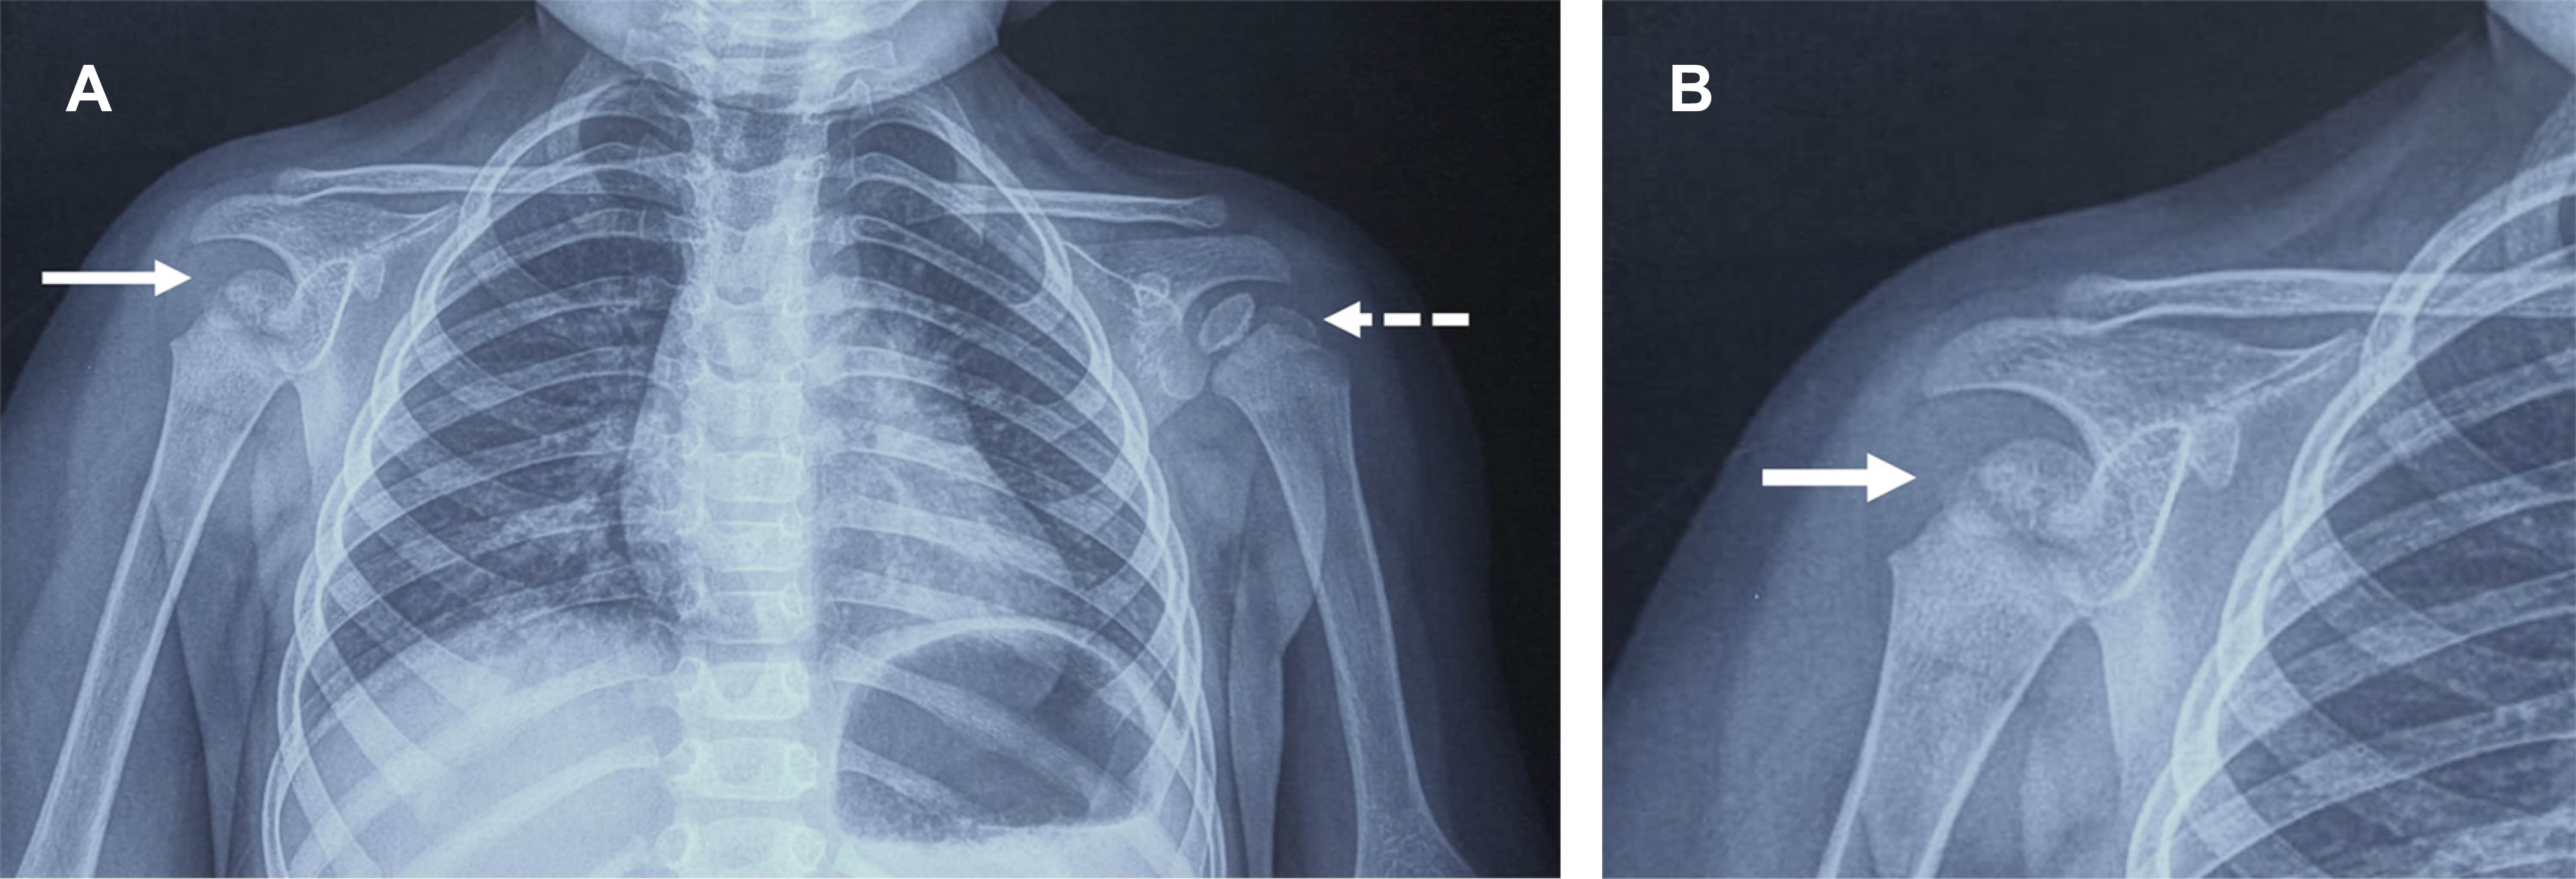

Femenino lactante mayor de 18 meses, con antecedentes perinatales sin problemas, quien dos horas antes presentó caída de su cuna, la madre la encontró en el suelo, con llanto y negativa a mover hombro derecho. A la exploración dirigida, se encontró: pérdida del contorno normal del deltoides, cabeza humeral derecha desplazada anteriormente y dolorosa al compararla con la contralateral, con imposibilidad pasiva y activa y para realizar flexión de hombro; clavícula, codo, antebrazo y mano normales, al igual que examen neurológico y llenado capilar. Con diagnóstico de luxación anterior de hombro derecho vs fractura humeral, se efectuó radiografía con la que se confirmó la luxación glenohumeral anterior (Figura 1); bajo sedación se efectuó reducción cerrada, la radiografía de control corroboró la reducción (Figura 2), se inmovilizó el miembro superior derecho con vendaje tipo Desault.

En cuanto a la radiografía anteroposterior de hombro en niños,5 los datos a valorar son: 1) las superficies articulares del húmero y la cavidad glenoidea deben aparecer como dos líneas paralelas con un espacio articular uniforme; 2) si la cabeza humeral se encuentra debajo de la apófisis coracoides, se debe contemplar una dislocación anterior del hombro; 3) si existe derrame articular o lipohemartrosis, se debe pensar en una fractura intraarticular; 4) en cualquier otra proyección (axial, radiografía en "Y" u oblicua apical), es necesario asegurarse de que la cabeza humeral se asiente sobre la cavidad glenoidea; 5) visualizar la epífisis y la metáfisis con acuciosidad, descartando fracturas; 6) si se detecta irregularidad o ruptura cortical, se debe contemplar una fractura humeral proximal, ya que la lesión más común en la infancia es una fractura fisaria y la luxación glenohumeral es muy rara.

Figura 1